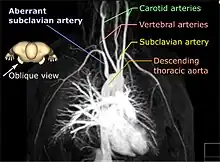

| Aberrant subclavian artery on MR angiography. | |

Aberrant subclavian artery, or aberrant subclavian artery syndrome, is a rare anatomical variant of the origin of the right or left subclavian artery. This abnormality is the most common congenital vascular anomaly of the aortic arch,[1] occurring in approximately 1% of individuals.[1][2][3]

This condition is usually asymptomatic.[1] The aberrant artery usually arises just distal to the left subclavian artery and crosses in the posterior part of the mediastinum on its way to the right upper extremity.[2] In 80% of individuals it crosses behind the esophagus.[2] Such course of this aberrant vessel may cause a vascular ring around the trachea and esophagus. Dysphagia due to an aberrant right subclavian artery is termed dysphagia lusoria, although this is a rare complication.[2][3] In addition to dysphagia, aberrant right subclavian artery may cause stridor, dyspnoea, chest pain, or fever.[1] An aberrant right subclavian artery may compress the recurrent laryngeal nerve causing a palsy of that nerve, which is termed Ortner's syndrome.[4]

The aberrant right subclavian artery frequently arises from a dilated segment of the proximal descending aorta, the so-called Diverticulum of Kommerell (which was named for the German radiologist Burkhard Friedrich Kommerell (1901–1990), who discovered it in 1936).[5][6] It is alternatively known as a lusorian artery.[1][3]